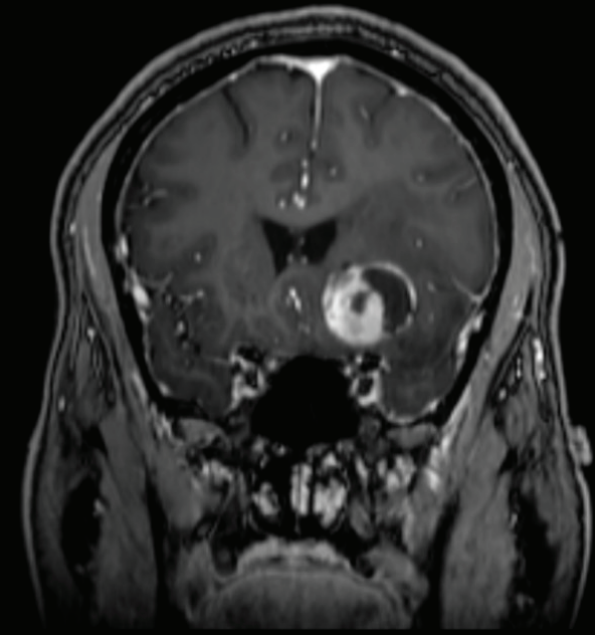

毛细胞星形细胞瘤约占全部儿童脑肿瘤的25%。在磁共振成像中,毛细胞星形细胞瘤通常是一种界限清楚的病变,通常具有囊性和结节状成分,可不均一地增...

毛细胞星形细胞瘤 是一种生长缓慢、边界较清的囊性星形肿瘤,是一种 良性胶质瘤 病理分型,WHO I级。 发病特点 毛细胞星形细胞瘤常发生于儿童和年轻人...

毛细胞星形细胞瘤,俗称毛星,是一种生长缓慢、边界明显、可伴囊性特点的良性肿瘤,WHO I级,好发于儿童和年轻人。毛星好发部位包括:1.视神经;2.视交...